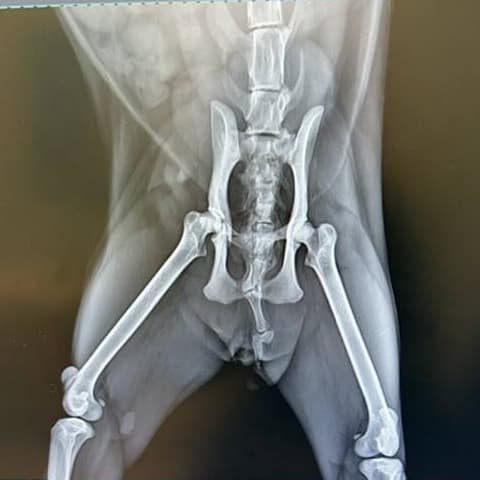

想領養混種貓 嗎?目前在新竹縣動物保護教育園區開放認養中,這隻女生貓正在找家,編號444141。歡迎聯絡新竹縣動物保護教育園區洽詢。備註: 疑似車禍,骨盆裂,入所時後肢拖行。115.3.24可行走跳躍